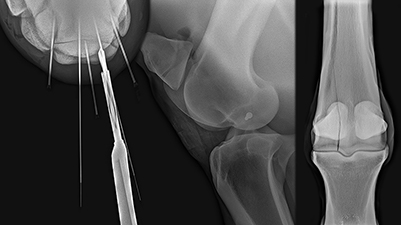

Advanced Course—Arthroscopic-guided Repair of Equine Articular Fractures and Treatment of Subchondral Bone Cysts

Gain clinical insight and hands-on experience treating intraarticular fractures and using implants to manage subchondral cystic lesions